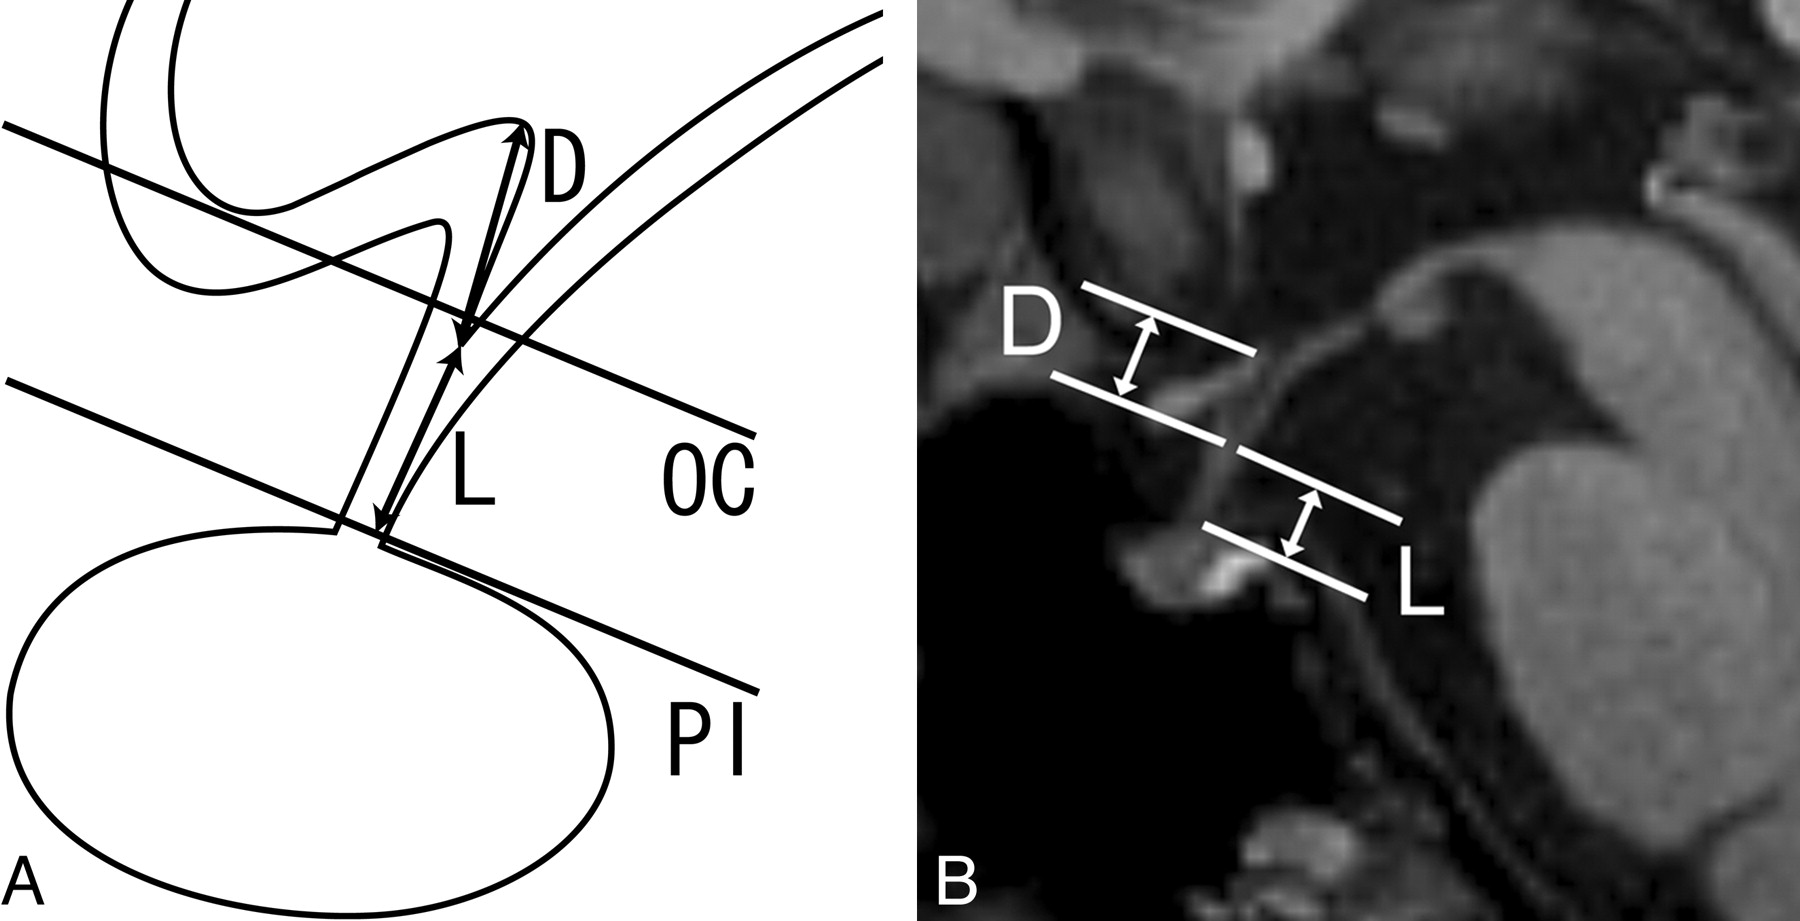

The diameter and the length of the pituitary stalk and the depth of the infundibular recess of the third ventricle were assessed for each subject (Fig 1). Both the AP and transverse diameters of the pituitary stalk were measured on T2-weighted oblique-axial images at 2 levels (at its insertion on the pituitary gland and at the level of the optic chiasm). These levels were chosen for measurement because Simmons et al7 measured the transverse diameter of the pituitary stalk on 1.5T MR imaging at these 2 levels. The length of the pituitary stalk and the depth of the infundibular recess were evaluated on the median sagittal MPRAGE image. The length of the pituitary stalk was defined and measured as the distance from the tip of the infundibular recess to the junction of the pituitary stalk and the pituitary gland along the course of the pituitary stalk. Six of 29 subjects (2 men and 4 women) had a convex superior margin of the pituitary gland in the current study, but there were no subjects in whom the superior gland margin protruded through the diaphragma sellae. Thus, the junction of the pituitary stalk and gland was angular and was identifiable in all subjects. The depth of the infundibular recess was defined and measured as the distance from the tip of the infundibular recess to the floor of the third ventricle at the anterior edge of the infundibular recess. Because the posterior wall of the infundibular recess often made a smooth transition to the floor of the third ventricle, or the tuber cinereum, the third ventricular floor at the posterior edge of the recess or at the midpoint of a line defined by the anterior and posterior margins was difficult to adopt as the superior extent of the infundibular recess. The ratio of the length of the stalk to the depth of the infundibular recess was also calculated for each subject.

The method of measurement of the pituitary stalk and infundibular recess. A, Schematic illustration of the pituitary stalk in the midsagittal plane demonstrates the depth of the infundibular recess (D) and the length of the pituitary stalk (L). The 2 lines indicate the levels at which the diameters of the pituitary stalk were measured (PI = the pituitary insertion of the pituitary stalk, OC = the level of the optic chiasm). B, Median sagittal MPRAGE image shows the depth of the infundibular recess (D) and the length of the pituitary stalk (L).